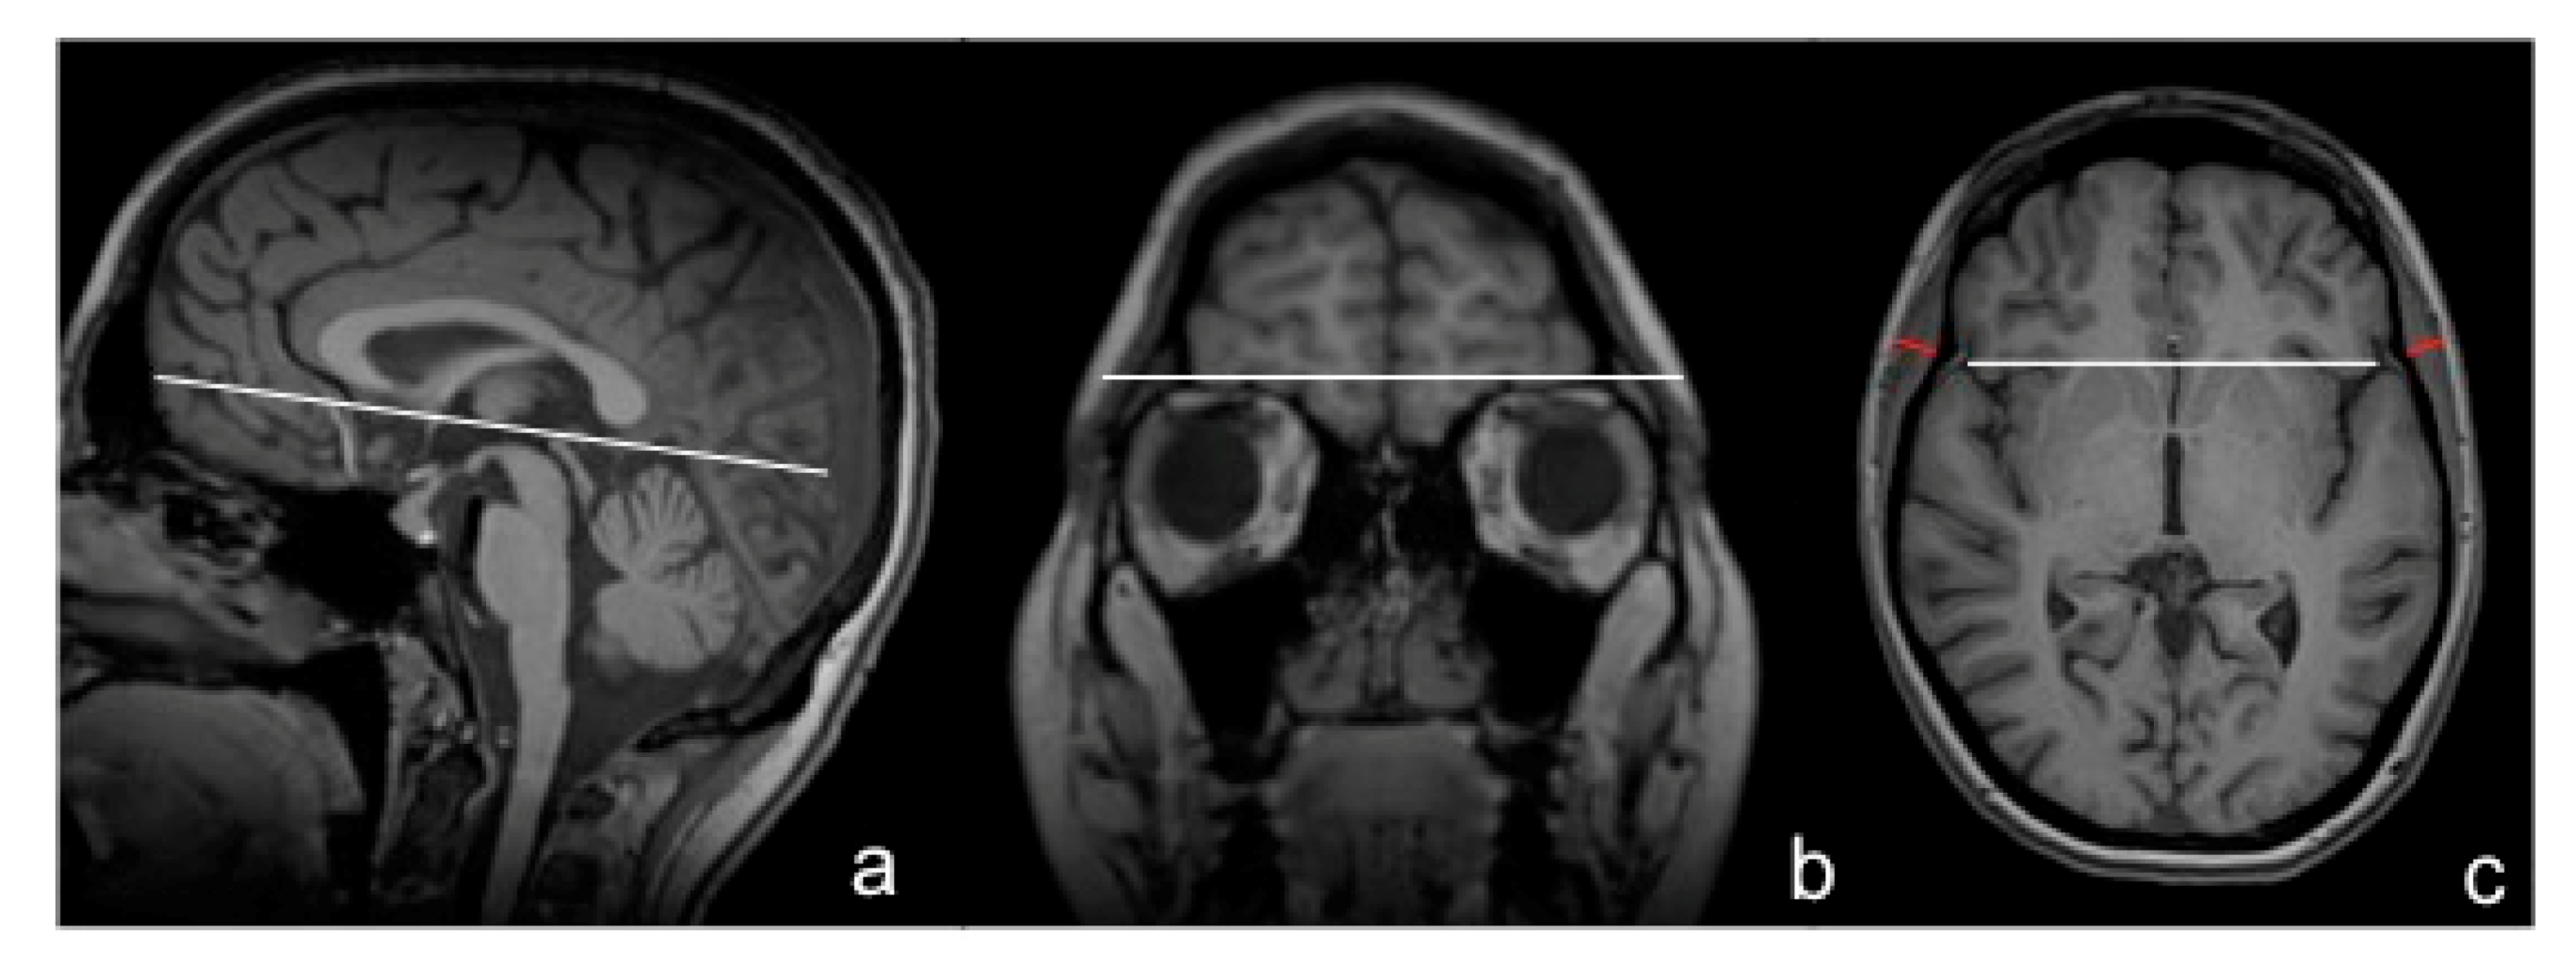

TMT was measured on isovoxel (1 × 1 × 1 mm3) T1-weighted MR images, perpendicularly to the long axis of the temporal muscle on an axial plane, which was oriented parallel to the anterior commissure-posterior commissure line, as described previously (Figure 2a) [21]. Predefined anatomical landmarks, such as the Sylvian fissure (anterior–posterior orientation) and the orbital roof (craniocaudal orientation) were used to guarantee a high reproducibility of TMT values (represented in Figure 2b,c). An example of TMT measurements in a healthy volunteer on T1-weighted, non-contrast-enhanced brain MR images is provided in Figure 2c. TMT was assessed on both sides in each individual. For further analysis, mean TMT was calculated by summing up those measurements and dividing them by two. All TMT measurements were performed by a board-certified radiologist (main reader = JF). If additional T1-weighted, contrast-enhanced MR images were available, TMT was also assessed by a second radiologist (JL). Temporal muscles indicating any kind of post-therapeutic changes that might have affected their thickness (e.g., muscle edema or atrophy due to craniotomy or radiation therapy) were excluded from further analysis.

Figure 2.

Anatomical landmarks represented with white lines (a–c) and an example of a TMT measurement in a healthy volunteer on T1-weighted, non-contrast-enhanced cranial MR images depicted in red (c).